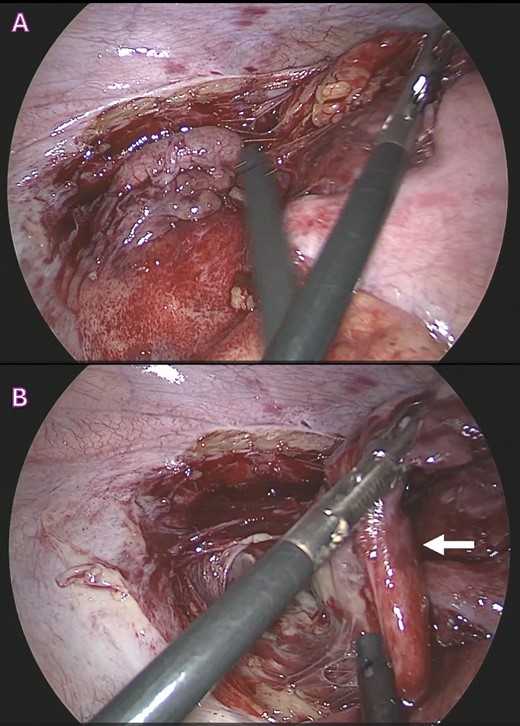

A 24-year-old Bangladeshi male presented to our emergency department with a 4-day history of right iliac fossa pain and fever. The patient denied experiencing diarrhea, vomiting, upper respiratory tract infection symptoms, radiation of pain, anorexia, testicular pain, or constipation. On examination, his temperature was 38.7°C, heart rate 108 bpm, blood pressure 116/66 mmHg, respiratory rate 18 breaths per minute, and oxygen saturation 100% in room air. Abdominal examination revealed localized tenderness and guarding in the right iliac fossa, along with positive rebound tenderness and Rovsing’s sign. Psoas sign and obturator sign were also elicited. Differential diagnoses included acute appendicitis, among other causes of abdominal pain, such as gastroenteritis, mesenteric lymphadenitis, incarcerated inguinal hernia, acute diverticulitis (less common in younger individuals), and pelvic inflammatory disease (less common in males). Investigations comprised laboratory tests, revealing elevated white blood cell count (14.1 × 103/μl) and C-reactive protein (CRP) levels (228.2 mg/L), and imaging via Computed Tomography (CT) abdomen and pelvis, which confirmed an acutely inflamed retrocecal appendix with a suspicious sealed perforation and an abscess cavity behind the cecum (Fig. 1). Blood cultures were collected in two anaerobic and two aerobic bottles at the time of admission. These bottles were placed in a BacT/Alert system (Becton Dickinson, NJ) for incubation. On Day 3, tests from both anaerobic blood culture bottles came back positive, at 52 and 59.5 hours, respectively, and gram stain analysis revealed the presence of Gram-negative bacteria (Fig. 2B) when observed under a microscope. Specimens were then grown on common blood agar plates under anaerobic conditions at 35°C. On Day 5 after presentation, moist and gray-white colonies were found (Fig. 2A). These were rapidly identified as O. splanchnicus using matrix-assisted laser desorption/ionization-time of flight mass spectrometry (MALDI-TOF MS) Biotyper (Library BDAL-11897-4274 Version 12, Bruker Daltonics, Bremen, Germany) on the same day. Treatment involved laparoscopic appendectomy (Fig. 3) and subsequent administration of intravenous amoxicillin–clavulanate 1.2 g three times a day for 10 days. The patient responded well to treatment, with normalization of laboratory values (discharge CRP: 67.7mg/L) and resolution of fever. Blood culture repeated after 72 h of intravenous antibiotics was negative.

Surgical images during laparoscopic appendectomy showing; (A) acutely inflamed retrocecal appendix buried retroperitoneally; (B) retroperitoneal large abscess pocket with ruptured appendix with thick pus and inflammatory exudates (white arrow).